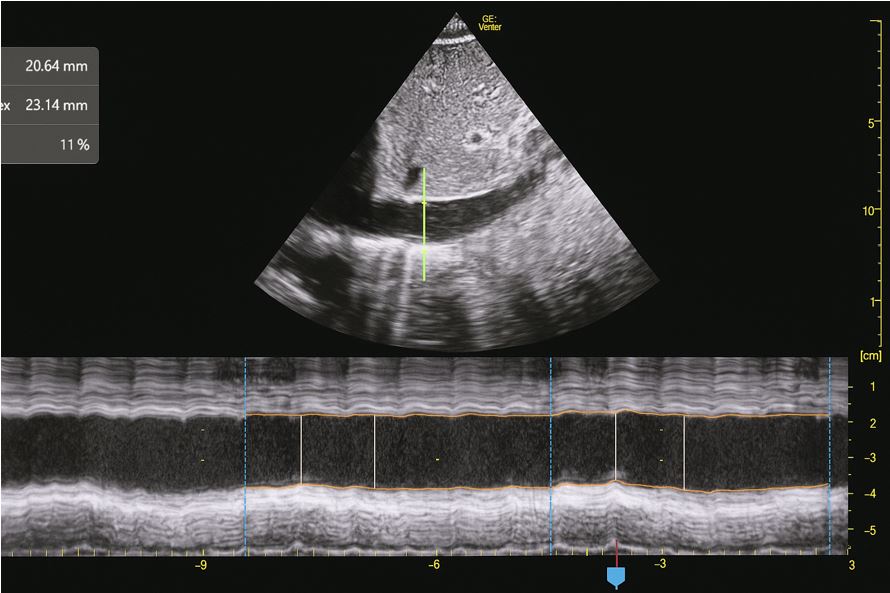

Refractory hypotension in amyloidosis patient: A case report

Refractory hypotension in AL amyloidosis

Kamonchanok Boonsri, Surat Tongyoo